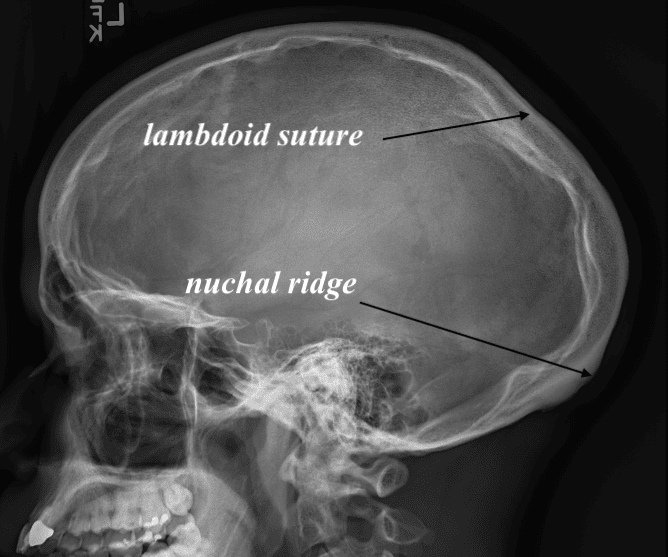

Desire to reduce prominent bony ridge on back of head.

Nuchal ridge skull reduction with high speed burring using a tunnel technique through a small scalp incision.

Desire to reduce prominent bony ridge on back of head.

Nuchal ridge skull reduction with high speed burring using a tunnel technique through a small scalp incision.